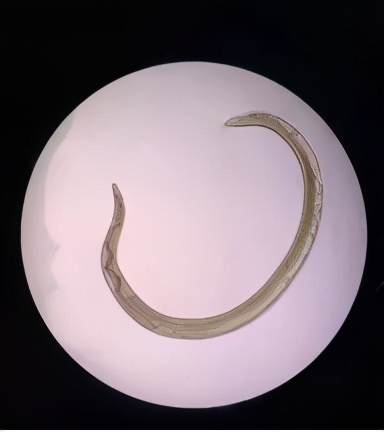

结膜吮吸线虫,虫体细长、半透明、淡红色,离开宿主之后变成乳白色。

体表除头尾两端外,还有横纹。

图源:网络